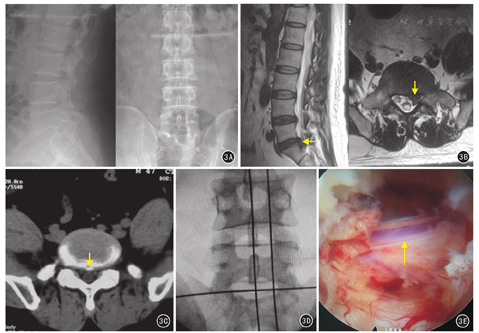

全身麻醉。患者俯卧位,C形臂X线机准确定位,取L5/S1后正中切口,长约3 cm。调整手术显微镜(OPMI VARI,德国Zeiss)放大4~6倍视野下切开棘上韧带,骨膜下剥离L5/S1患侧椎板至关节突,椎板减压,清除椎板外组织,松解神经根,探查并清理椎间隙,取出突出或脱出髓核。见图1。